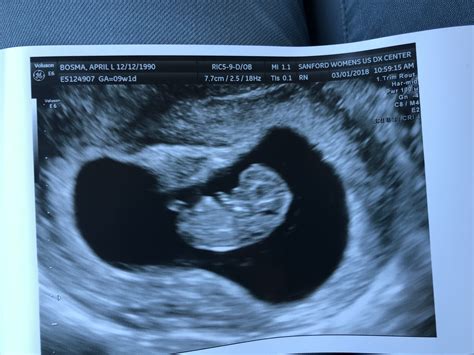

During a 7 week pregnancy sonography, the ultrasound technician will look for several key indicators of fetal development. These include:

• The presence of a gestational sac, which is the earliest sign of pregnancy visible on ultrasound.

• The yolk sac, which provides early nutrition to the embryo.

• The embryo itself, which should be visible as a small, curved structure within the gestational sac.

• The fetal pole, which is the earliest visible part of the embryo.

• The heartbeat, which may be detectable by this week, although it is not always visible at 7 weeks.

If the heartbeat is not detected, it is not necessarily a cause for concern, as it can sometimes be too early to see. The technician will also measure the size of the gestational sac and the crown-rump length (CRL) of the embryo, which helps to estimate the gestational age and ensure that the pregnancy is progressing normally.

At 7 weeks, the embryo is still very small, measuring about 10,000 times smaller than a newborn baby. However, significant development is occurring. Some of the common findings during a 7 week pregnancy sonography include:

• The embryo is curved, with a distinct head and tail.

• The neural tube, which will eventually form the brain and spinal cord, is beginning to close.

• The heart is developing rapidly, and the heartbeat may be visible.

• The placenta is starting to form, providing essential nutrients and oxygen to the embryo.